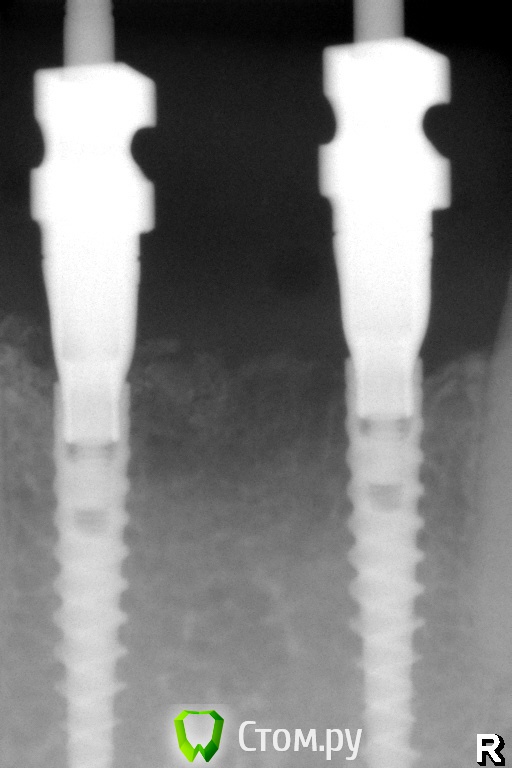

Pavel-Pskov Опубликовано 4 ноября, 2014 Автор Поделиться Опубликовано 4 ноября, 2014 Еще пара снимков.Через год. Ссылка на комментарий

АнтонТЛТ Опубликовано 4 ноября, 2014 Поделиться Опубликовано 4 ноября, 2014 Какие-то странные абатменты, как-будто в имплантаты заходят на 1мм. Ссылка на комментарий

doca Опубликовано 4 ноября, 2014 Поделиться Опубликовано 4 ноября, 2014 Какие-то странные абатменты, как-будто в имплантаты заходят на 1мм.техник ,по ходу, подрезал их зачем-то. может быть там винтовая фиксация с вклейкой Ссылка на комментарий

Pavel-Pskov Опубликовано 6 ноября, 2014 Автор Поделиться Опубликовано 6 ноября, 2014 техник ,по ходу, подрезал их зачем-то. может быть там винтовая фиксация с вклейкойДа. Ссылка на комментарий